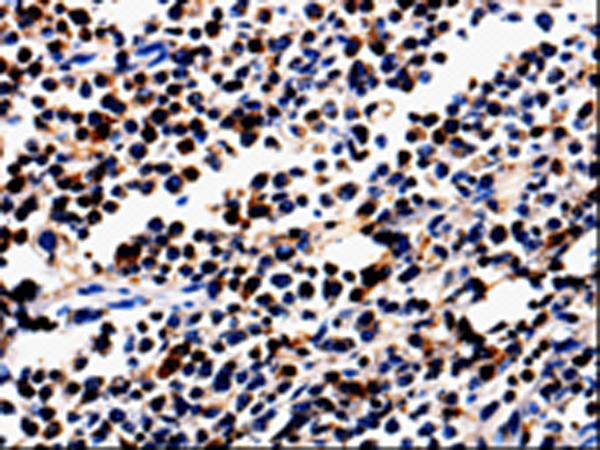

分类: 科研抗体货号: P00147别名: ANG3; ARP1; AngY; ANGPT3; UNQ162; dJ595C2.2应用: IHC反应种属: Human, Mouse